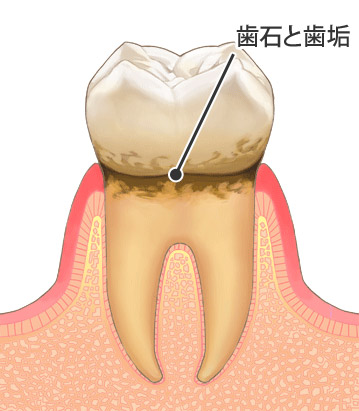

この程度であれば、レーザーを用いたり歯垢・歯石を十分に取り除いたりすることで、もとの状態に戻す事が可能です。

歯肉が炎症を起こし、歯槽骨の吸収を起こし始めます。